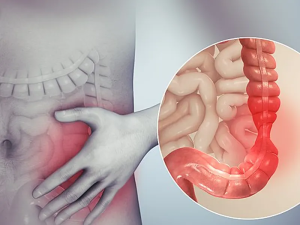

خون در مدفوع یکی از نشانههای نگرانکنندهای است که میتواند از مشکلات سادهای مانند هموروئید یا شرایط پیچیدهتری مانند سرطان روده بزرگ ناشی شود. مشاهده خون در مدفوع، به ویژه اگر به صورت مکرر اتفاق بیفتد، نیازمند توجه فوری پزشکی است. این علامت ممکن است ناشی از مشکلات مختلفی در دستگاه گوارش باشد که هر کدام نیازمند درمان خاص خود هستند. در این مقاله، به بررسی علل شایع خون در مدفوع، علائم همراه، روشهای تشخیص، و روشهای درمانی پرداخته میشود. همچنین بهترین پزشکان متخصص گوارش و کبد در تهران برای درمان این مشکل معرفی خواهند شد. علل خون در مدفوع هموروئید: یکی از شایعترین علل خون در مدفوع، هموروئید یا